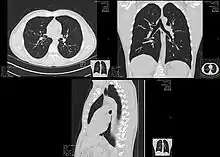

肺部

在肺部組織的診斷上,X射线计算机断层成像對於急性或是慢性的變化都有很高的診斷價值,在觀察一些人體內空氣的變化,例如肺炎或是腫瘤,一般不需顯影劑就有很好的效果。而一些間質組織的變化(肺氣腫,肺纖維化等等),可以用薄切面的高解析設定來重建,称作高解析度電腦斷層(HRCT);筛检早期肺癌,可利用低剂量胸部电脑断层(LDCT);而要評估縱隔腔和肺門部分的淋巴腺腫大,則需要靜脈顯影。

胸腔斷層血管攝影(CTPA)是一個需要用精確快速的時間來作對比劑注射再加上高速的螺旋式描掃器才能完成的檢查,近來也用在作肺栓塞和動脈剝離的評估。當胸腔X光檢查出現異常或是懷疑異常等,只要是非急性的,電腦斷層都是首推的進一步檢查。